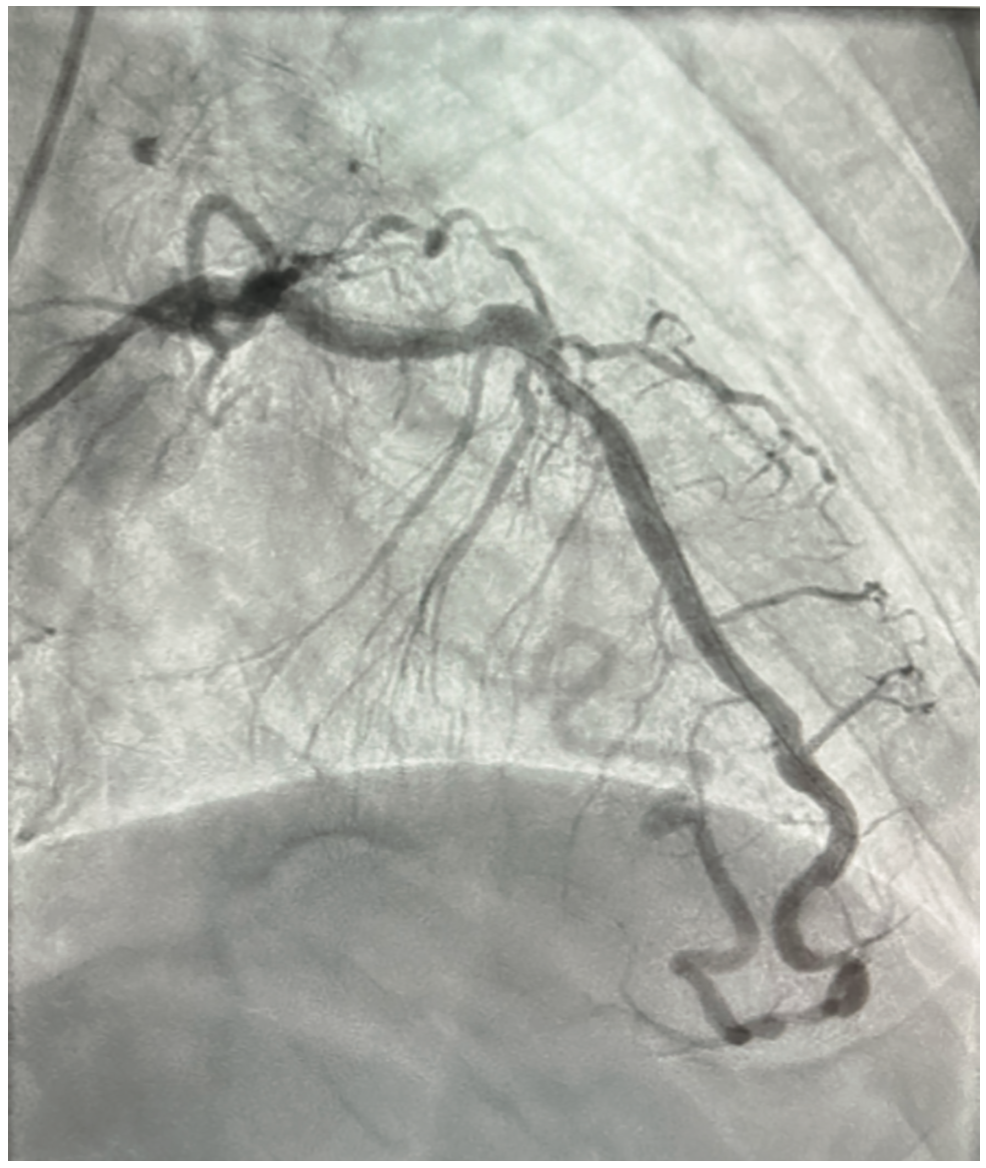

The patient is a 76-year-old male with a past medical history of hypertension, peripheral arterial disease (PAD), myocardial infarction (MI) two years ago, and hyperlipidemia, presenting with dyspnea on exertion. He was suspected of having coronary artery disease (CAD) after an abnormal stress test, and subsequently underwent a left and right coronary artery catheterization through the right radial artery. The patient was given 2 mg of midazolam and 200 mcg of fentanyl intravenously for a total sedation time of less than a minute. Access was achieved using a modified Seldinger technique with a 6 French catheter placed in the right radial artery. A 5 French catheter was then placed to engage the left coronary artery. Angiography showed a patent left main coronary artery and an 80% stenosis in the mid LAD. There was a small, patent, non-dominant LCX, and a dominant RCA with a chronic total occlusion and evidence of left and right collaterals. The ejection fraction was 60% and left ventricular end diastolic pressure was 14 mmHg. The LAD was noted to have an unusual course across the anterior heart. The extension of the LAD wrapped around the apex and supplied a large portion of the posterior heart, providing left and right collaterals. After further consideration, this vessel was identified as the left obtuse marginal artery coming off the LAD rather than the left circumflex artery, suggesting an anomalous coronary artery (Figures 1-3). Due to the patient’s multivessel CAD, cardiothoracic surgery was consulted for coronary artery bypass graft (CABG) evaluation. The patient underwent off-pump CABG x2 with left internal mammary artery to the LAD and a reverse saphenous vein bypass graft from the aorta to the distal RCA. He tolerated the procedure well and was subsequently taken to the cardiovascular intensive care unit in stable condition.